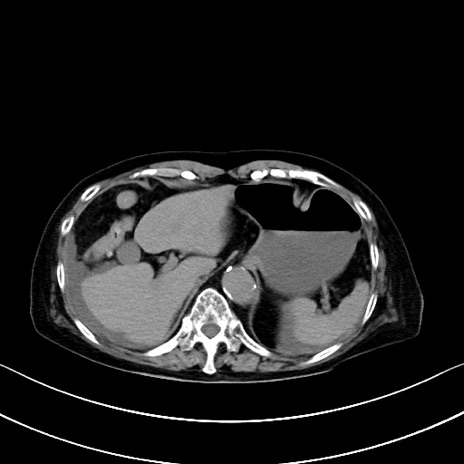

横断像